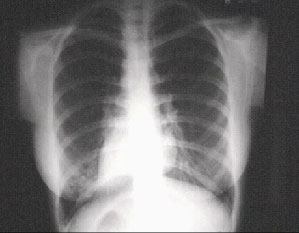

This chest X ray demonstrates dextrocardia, with the cardiac apex on the right. Note that the stomach bubble is also on the right, thus demonstrating situs inversus. While dextrocardia may be found in patients who are otherwise normal, when it occurs in the absence of situs inversus, a very high incidence of congenital heart disease is found.